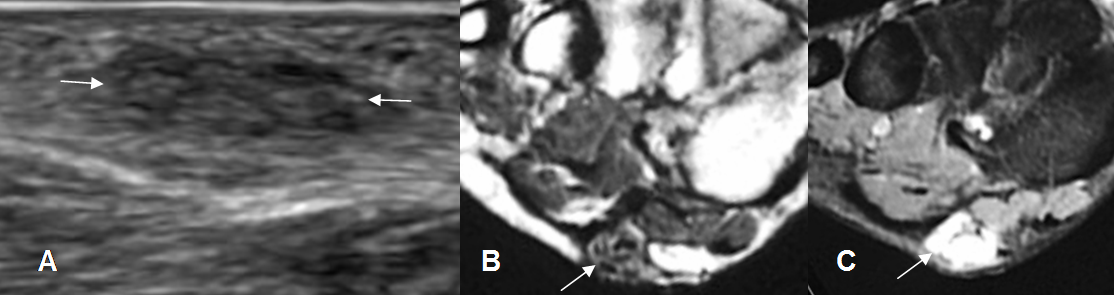

Fig 112. Fibromatosis plantar.

A: Ecografía vista sagital. Imagen hipoecoica y parcialmente definida en la planta del pie.

B: RM coronal en T1 y C: RM coronal en STIR. Area redondeada y superficial, que

reemplaza la grasa, hipointensa en T1 e hiperintensa en STIR.